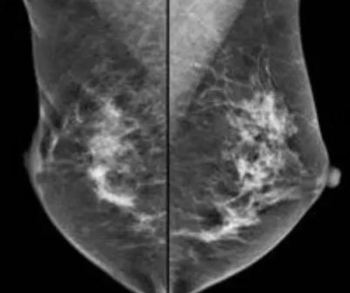

In separate test sets of Israeli women and United States women who had either ductal carcinoma in situ or invasive breast cancer, emerging artificial intelligence (AI) algorithms achieved an area under the curve (AOC) of 88 percent and 80 percent, respectively, for malignancy detection.